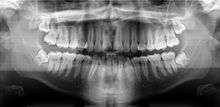

A dental panoramic radiograph, showing the maxilla and mandible, all the teeth including the "wisdom teeth," the frontal and maxillary sinuses, the nasal cavity and the temporomandibular joint and other near by head and neck anatomy. | |

A panoramic radiograph is a panoramic scanning dental X-ray of the upper and lower jaw. It shows a two-dimensional view of a half-circle from ear to ear. Panoramic radiography is a form of tomography; thus, images of multiple planes are taken to make up the composite panoramic image, where the maxilla and mandible are in the focal trough and the structures that are superficial and deep to the trough are blurred.